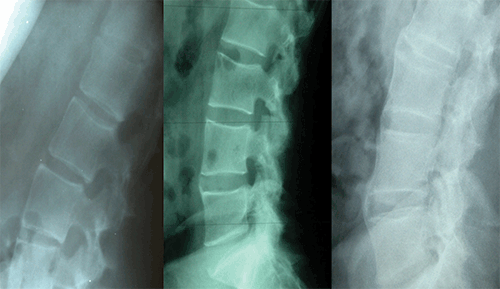

This video describes the pathology behind the radiological features of Ankylosing spondylosis . It includes the following features . Ankylosing Spondylitis Sacroiliitis Vs Normal are a topic that is being searched for and appreciated by netizens now. You can Download the Ankylosing Spondylitis Sacroiliitis Vs Normal here. Download all royalty-free pix. MRI lesions in the sacroiliac joints of patients with spondyloarthritis, To cite: Maksymowych WP, Lambert RG, Østergaard M, et al. Annals of the Rheumatic Diseases 2019. Published Online First: 17 .

• pics Ankylosing Spondylitis Sacroiliitis Vs Normal grading of the si joint in as patients is shown on the ap view of the download scientific diagram

• Grading Of The Si Joint ... | 466x466 px